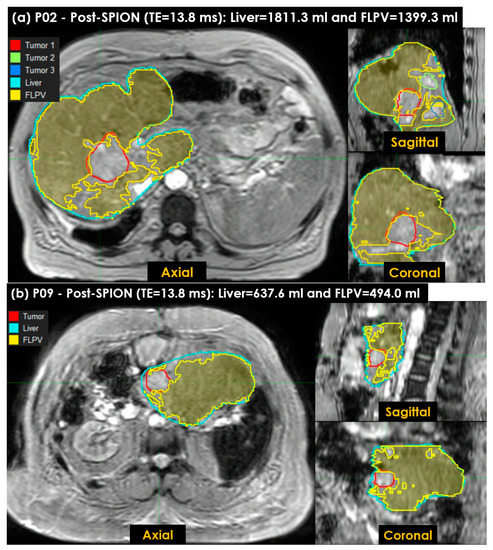

This study also utilized the ONLY-POSTR2* approach to characterize the FLPV with our auto-contouring tool. Figure 8 shows the FLPV identified in the auto-contouring tool with THRES-MEANR2* in the ONLY-POSTR2* approach. The FLPV was clearly identified with minimal overlapping for three tumors in patient P02 (Figure 8a) and a tumor in P09 (Figure 8b). The FLPVs in P02 and P09 were 1399.3 mL (77.3%) out of 1811.3 mL and 494.0 mL (77.5%) out of 637.6 mL, respectively. The three tumors in P02 and the single tumor in P09 demonstrate the efficiency of auto-contouring the FLPV on axial, sagittal and coronal 3D planes.

Figure 8. The functional liver parenchyma volume(s) FLPV(s), identified using the THRES-MEANR2* of the second ONLY-POSTR2* approach in an auto-contouring in-house tool, were overlaid on liver images. (a) Three tumors in patient P02, contoured in red (first tumor), green (second tumor) and blue (third tumor), are illustrated to demonstrate the efficiency of the in-house tool for identifying the FLPV; (b) a single tumor in patient P09, contoured in red, is also illustrated. Similarly, both the FLPVs of P02 and P09 are clearly distinguished from all tumors with minimal overlap between the FLPVs and non-FLPVs (tumor, hepatic vessels, liver fibrosis and scarring associated with hepatic cirrhosis).